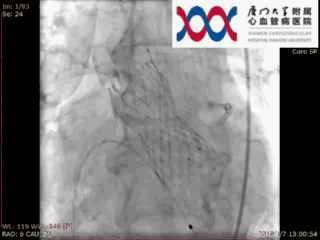

瓣膜释放后造影

多年的病史,让庄爷爷深刻体会疾病带来的痛苦。现在庄爷爷活动力明显下降,除了静卧休息,动动就觉得气促难受。由于庄爷爷已是98岁高龄,若进行外科开胸手术会大大增加术后死亡率和并发症的发生风险。对于庄爷爷的病情,厦门大学附属心血管病医院心脏团队联合麻醉科,心超科,放射科,手术室,重症监护室等多学科对术前准备,手术方案及术后护理等进行详细讨论。2019年1月7日,王焱院长及王斌主任心脏团队为庄爷爷实施了经股动脉主动脉瓣置换术,手术非常顺利。瓣膜释放后心超及造影显示跨瓣压差0mmHg,无瓣周漏,无返流。这是目前国内接受经股动脉主动脉瓣置换微创手术的最高龄患者。